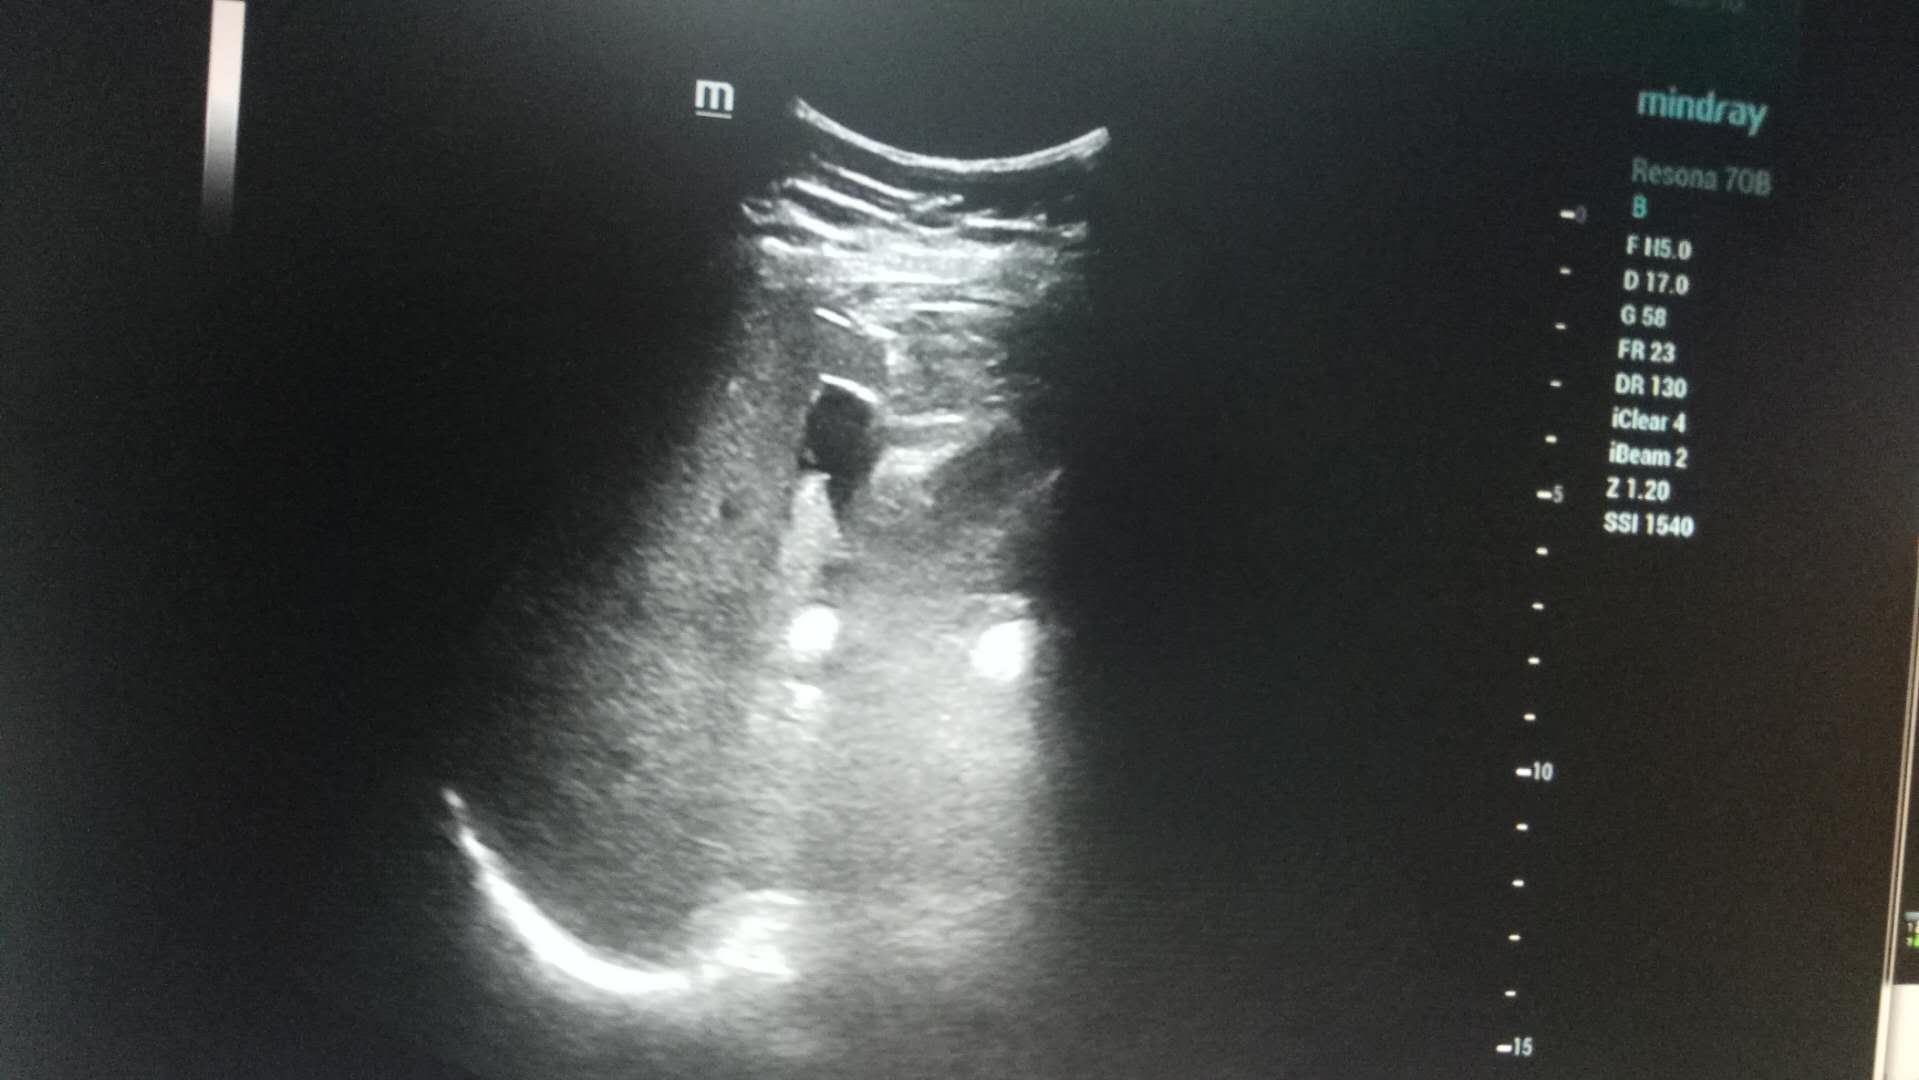

近日,探花av 超声科在高陵区医院成功开展了一例超声引导下肝囊肿抽吸硬化治疗术。患者前段时间查出肝囊肿,因开腹手术风险性大且痛苦,遂联系了高陵区医院超声科,在探花av 超声科主任展小军与对口支援医生杨艳秋的紧密配合下,短短30分钟,通过一根穿刺针,直径近7cm的肝囊肿就被完全抽吸硬化完毕,患者生命体征平稳,休息几小时后已活动自如。

超声介入微创诊疗技术是在实时超声的监视和引导下,完成各种穿刺、活检以及抽吸、插管、注药治疗等操作,达到与外科手术相当的效果,具有创伤小、恢复快、无辐射、介入治疗定位精确等优点。可治疗全身各部位囊肿,尤其是巧克力囊肿效果更佳,还有全身各部位肿瘤的活检和治疗,超声引导下微创治疗是未来医学发展方向。